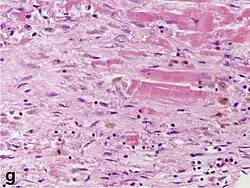

Micrograph of a myocardial infarction (ca. 400x H&E stain ) with prominent contraction band necrosis.

Histopathological examination of the heart may reveal infarction at autopsy. Gross examination may reveal signs of myocardial infarction.

Under the microscope, myocardial infarction presents as a circumscribed area of ischemic, coagulative necrosis (cell death). On gross examination, the infarct is not identifiable within the first 12 hours.[22]

Although earlier changes can be discerned using electron microscopy, one of the earliest changes under a normal microscope are so-called wavy fibers.[23] Subsequently, the myocyte cytoplasm becomes more eosinophilic (pink) and the cells lose their transversal striations, with typical changes and eventually loss of the cell nucleus.[24] The interstitium at the margin of the infarcted area is initially infiltrated with neutrophils, then with lymphocytes and macrophages, who phagocytose ("eat") the myocyte debris. The necrotic area is surrounded and progressively invaded by granulation tissue, which will replace the infarct with a fibrous (collagenous) scar (which are typical steps in wound healing). The interstitial space (the space between cells outside of blood vessels) may be infiltrated with red blood cells.[22]

These features can be recognized in cases where the perfusion was not restored; reperfused infarcts can have other hallmarks, such as contraction band necrosis.[25]